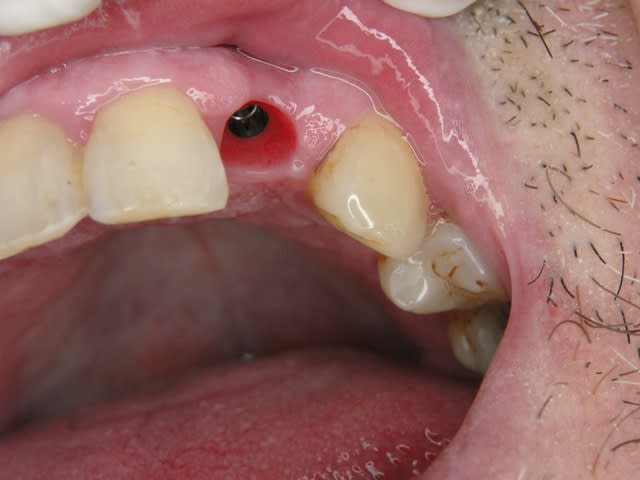

Photos d'un cas d'extraction implantation immédiate, stabilité primaire (de mémoire) assez élevée.. 60/70 N ..démontage du gingiva clips et du shuttle, pilier serré 40N, couronne procera

Merci pour le cas, bien fait. Belle présentation photo.

Le contour gingival est net, belle guérison, c'est à combien de semaine ?

Oui je sais pour le ciment... j'utilise d'ailleur ce cas et cette radio dans une présentation pour mettre en garde sur le risque au moment du scellement de voir du ciment fuser sous la limite prothétique vers la col de l'implant..galère à éliminer...Personnellement je préfere plutot utiliser des piliers à usiner (maintenant disponibles voir shop online pour photos) au lieu des strandarts meme si il y a deux hauteurs/col implantaire en 1 et 3mm aujourd,hui disponibles..A l'époque de ce cas il n'y avait que les 1 mm et la limite est un "poil" trop profonde.

La pose de la couron nec'est faite 8 semaines apres l'extraction implantation immédiate, la particularité de ce systeme permet de ne pas démonter le shuttle ni la gingivaclip pour l'empreinte..je pense que ca aide bien à la qualité gingivale...radio controle ci jointe